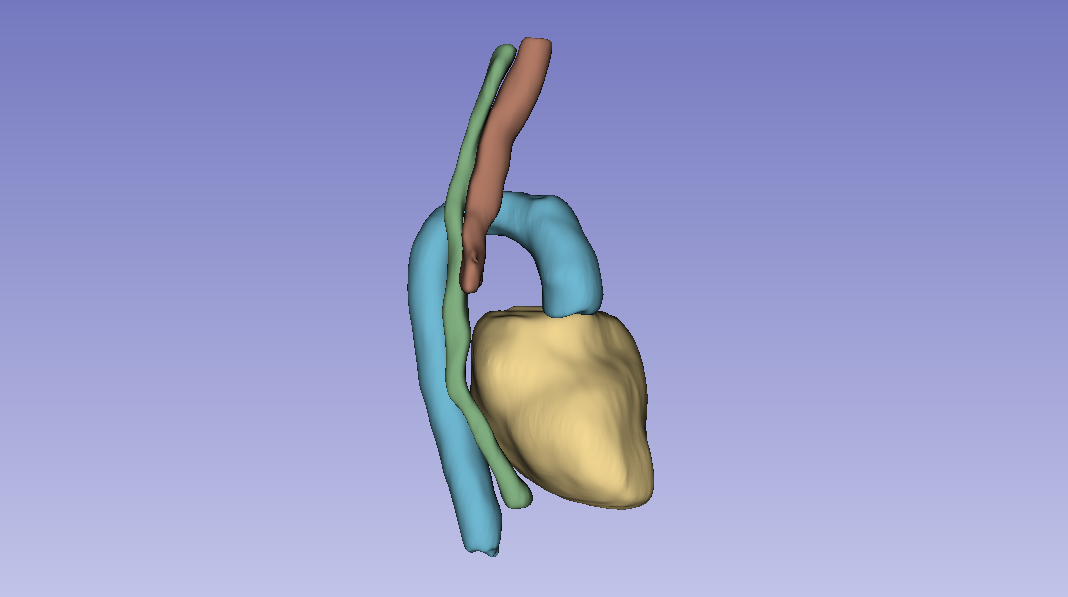

Overview

Group project for AI for Medical Imaging (UvA, part of the VU M.Sc. AI program) on the SegTHOR challenge: segmenting four thoracic organs (heart, esophagus, trachea, aorta) from 3D CT volumes. We compared a 2D baseline (ENet), a custom 2D architecture (CustomNet, U-Net based), and 3D Full-Resolution nnU-Net.

Before any modelling, the heart annotations were misaligned for several patients. Patient 27 had two ground truth files in the dataset, one correct and one misaligned. We tried to fix the misalignment with Elastix (rigid + affine transformations), but no parameter combination got the heart to register cleanly.

The fix that worked was a centroid-then-rotation approach: subtract the misaligned heart's centroid from the correct centroid to get a translation vector, then sweep rotation angles in the transverse plane and pick the one that maximised IoU. The optimal correction was a −26.6° rotation around the superior-inferior axis. We then applied the same transformation across the dataset.

- The interesting nuance is the heart. Heart Hausdorff actually got worse for CustomNet despite a better Dice, because both CustomNet and nnU-Net over-segment the heart. Heart precision dropped from 0.92 (baseline) to 0.89 (CustomNet), and dropped further on nnU-Net. Recall went up; precision went down. Net Dice still improved but the failure mode is real.

3D Full-Resolution nnU-Net is the clear winner for this task: significantly better Dice and recall, smoother predictions (post-processing's connected-component analysis cleans up the artefacts the 2D models leave). The cost is that it over-segments the heart, which would matter for clinical deployment and is the obvious next-step refinement.